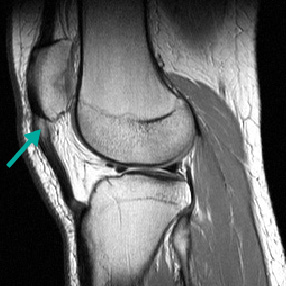

Ressonância nuclear magnética (RNM) demonstrando tendinopatia leve a moderada do centímetro proximal do tendão patelar, caracterizado pelo espessamento e sinal anormal no tendão

Do acervo pessoal de James Wang, PhD